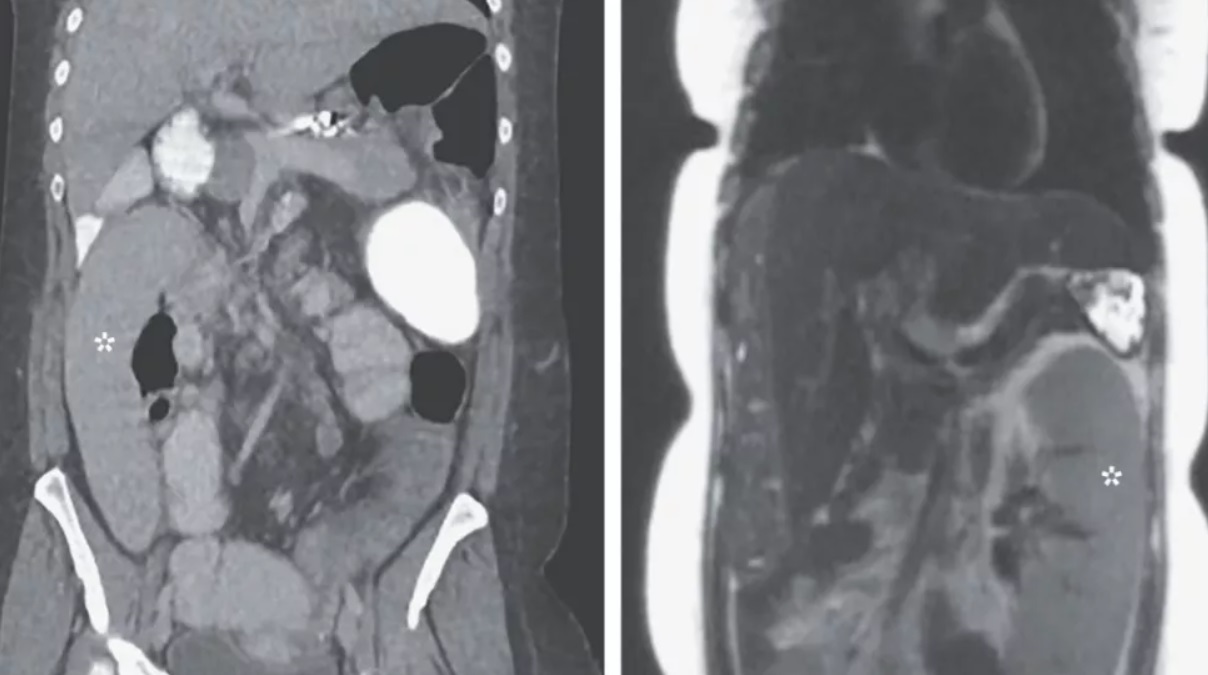

В Волынской области хирурги удалили 20-килограммовую раковую опухоль: история пациентки (фото 18+)

Опухоль могла лопнуть в любой момент, спровоцировать сильное кровотечение, и женщина могла умереть. ru.tsn.ua »

Врачи удалили у женщины гигантскую опухоль: ее вес больше, чем у пациентки

24-летняя женщина не хотела идти в больницу, однако впоследствии уже не могла нормально жить из-за опухоли, которая весила больше, чем она. comments.ua »